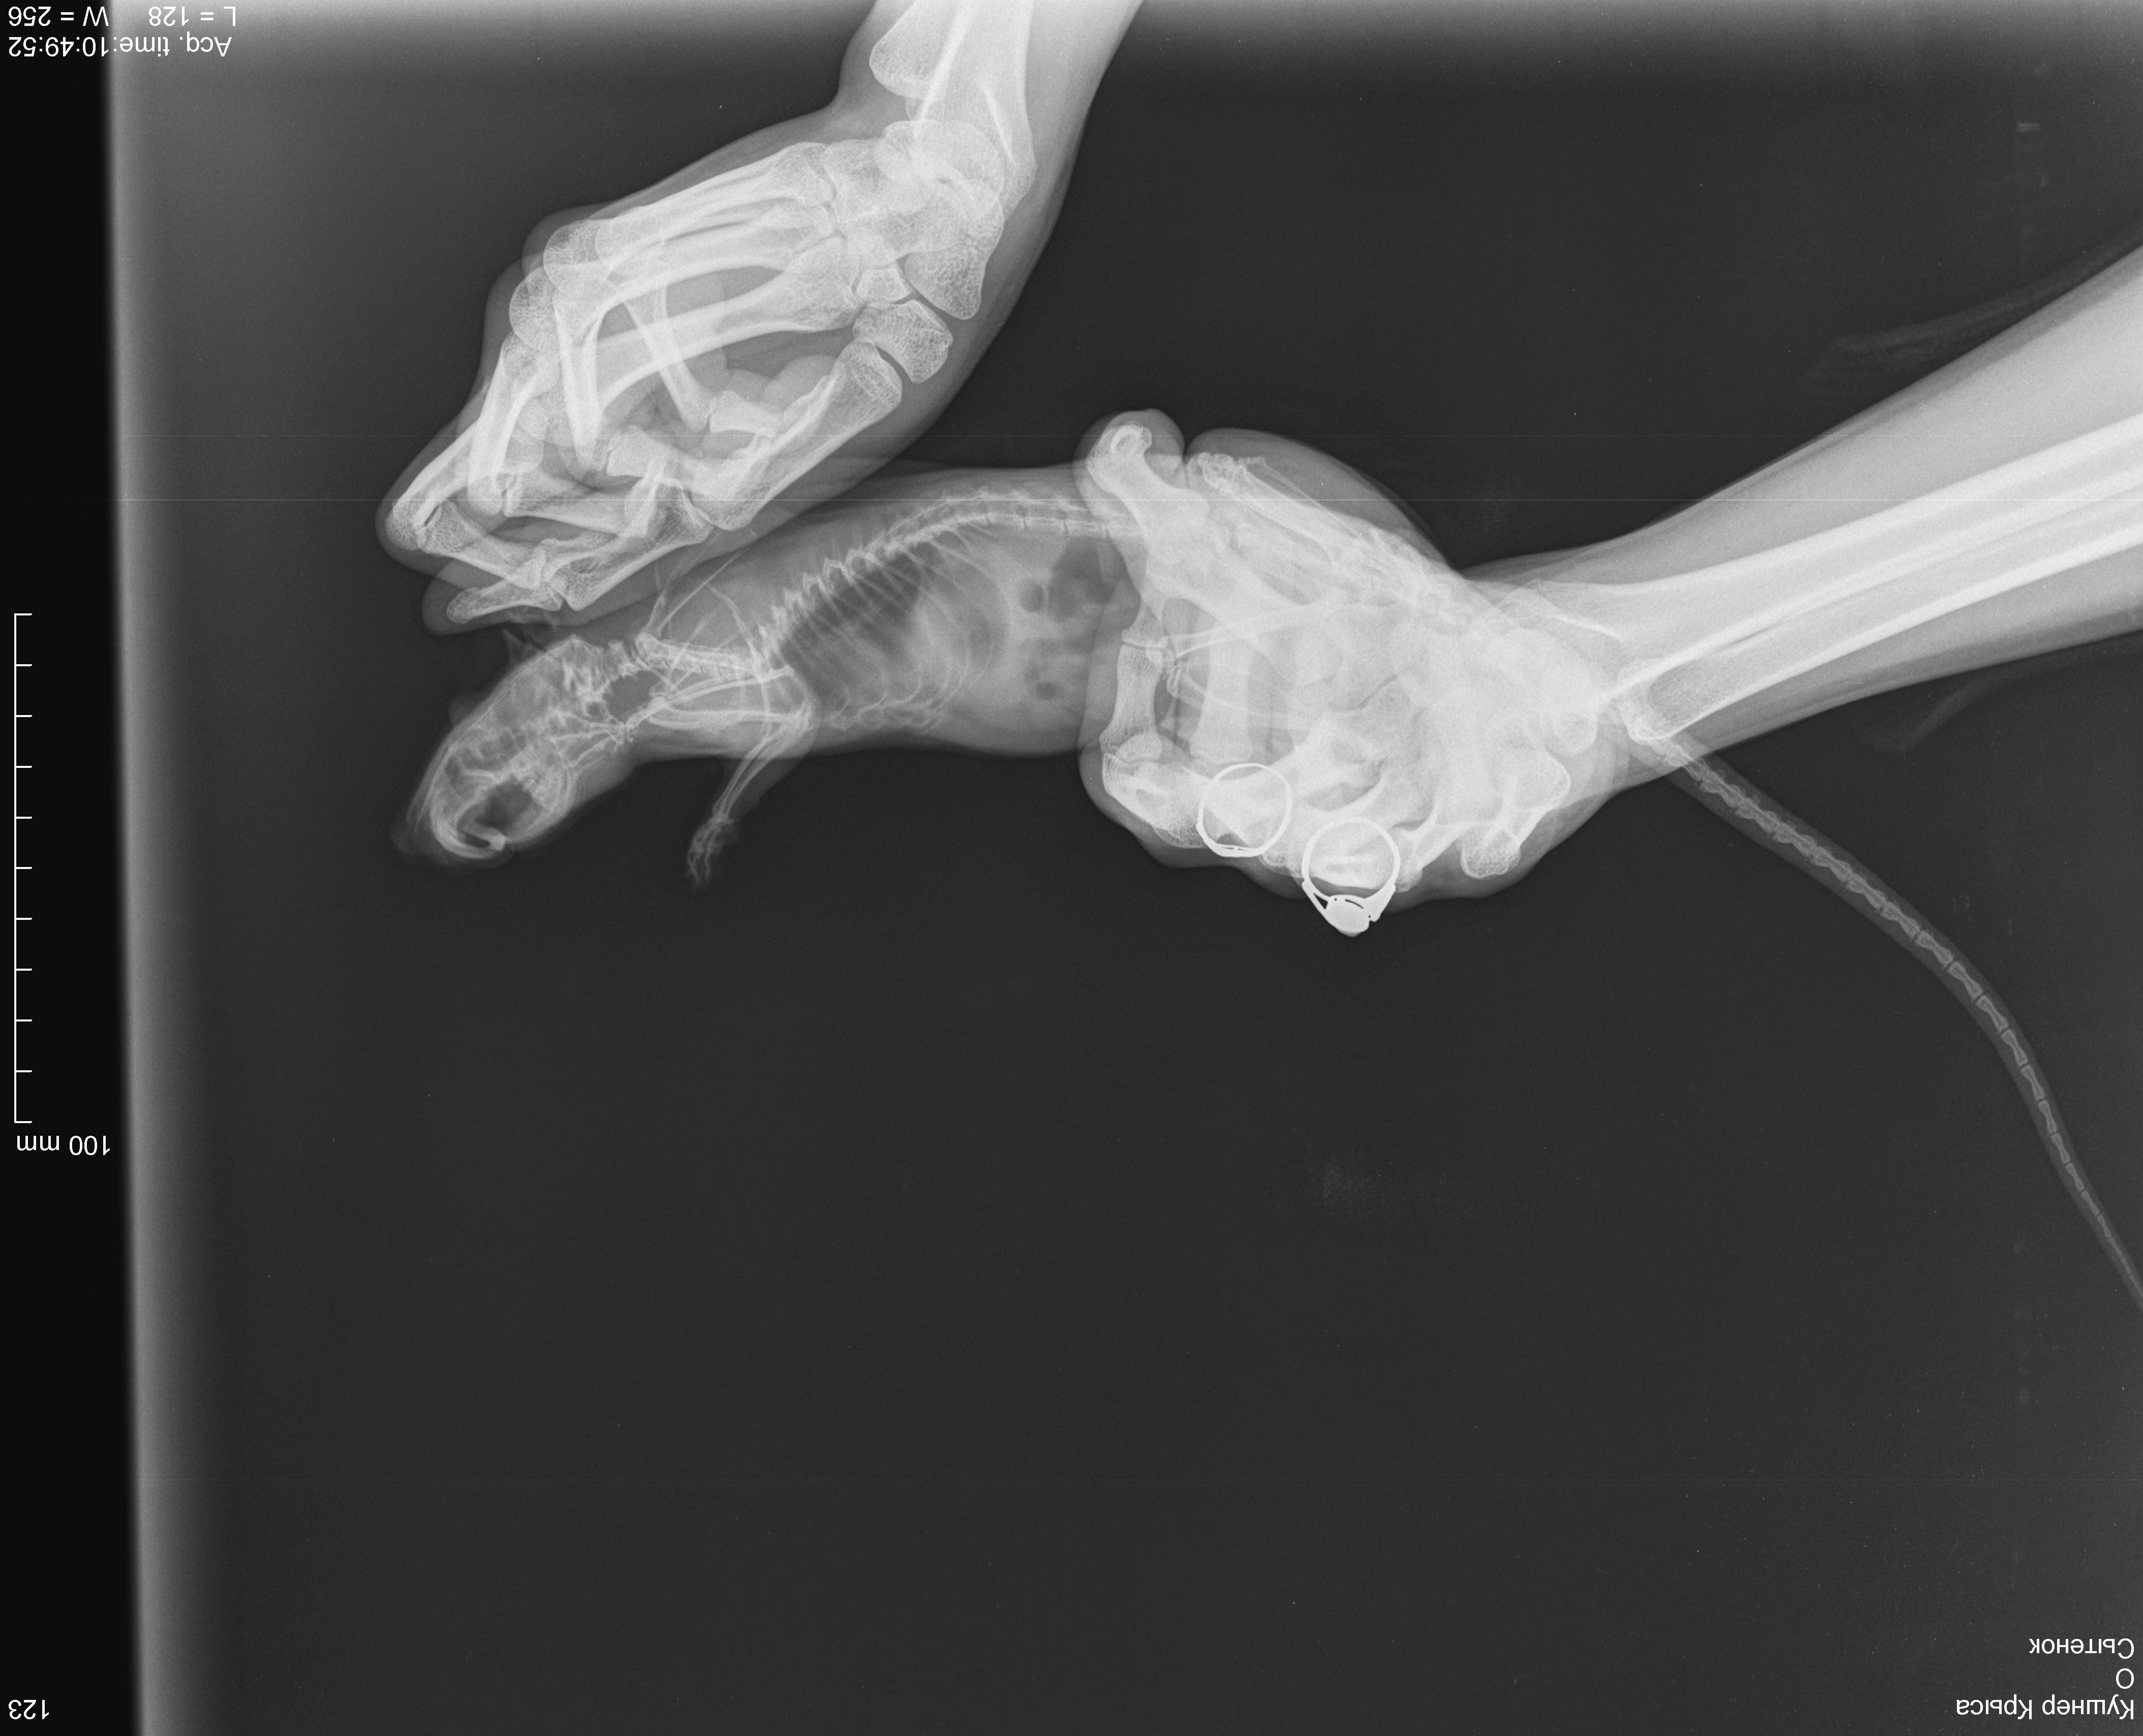

6 декабря свозила к ветеринару, послушали - услышали хрипы, больше слева, сделали рентген, врач сказала, что вероятнее всего пневмония, назначила синулокс 0,15мл в/м 1 раз в день, катозал 0,3мл 1 раз в день. По-моему стало немного получше, начал умываться. Дома пару раз пытался попить, но такое ощущение, словно захлебываться начинает и перестает, стал незначительно активнее. 8,9 декабря возила его на оксигенотерапию по 1 разу по 20минут, в состоянии особо изменения не заметила. 10 числа ближе к вечеру - крыса сидит на одном место, тяжело дышит, дышит боками, хрипы более выраженные, голова опущена вниз, беспокойный, в руки не дается. Повезла к другому врачу (рабочее время моего закончилось) - сказал, что вероятнее всего отёк легких, сделал инъекцию дексаметазона 0,05мл в/м. Спросила про диуретики, сказала, что не надо, так как дексаметазон будет выполнять эту функцию в том числе. :/ Отметил, что если не поможет, то наварное ничего уже не поможет. Сегодня, 11 числа, стало незначительно лучше, поехала к своему врачу, она была на выезде, приняла другая девушка, сказала что не отёк, т.к. хрипы должны быть другие. Назначила ингаляции беродуала и соответственно продолжать назначенную терапию.

Я не знаю, продолжать ли терапию, или её стоит поменять или я только мучаю крысу и ей врят ли уже помогут. Есть ли смысл покупать беродуал? Посмотрите на снимки, пожалуйста, действительно ли пневмония, а не онко? В прямой проекции видно затемнение в проекции шейных позвонков, но на боковой его не вижу, врачи сказали, что это надгортанник ](*,) , хочется быть уверенной, что не какое-нибудь инородное тело.

Кушнер Крыса_DX_20181206_104952_1.jpg